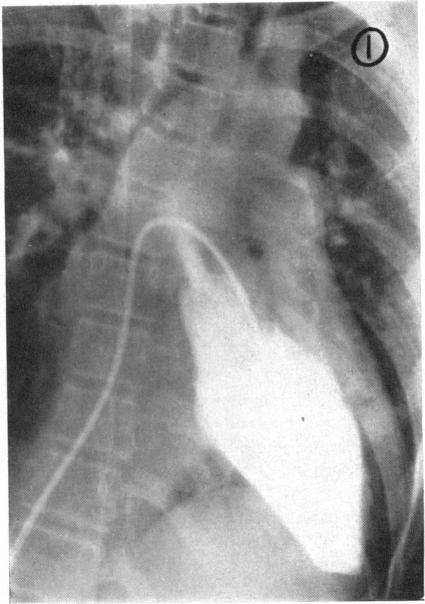

TRANSSEPTAL LEFT HEART CATHETERIZATION.

Br Heart J. 1964 Jan;26(1):33-8. doi: 10.1136/hrt.26.1.33.